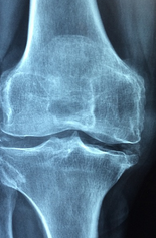

무릎 관절은 무릎을 구성하는 뼈인 대퇴골, 슨골, 장골이 부착되어 이루어진 관절로, 운동과 일상 생활에서 매우 중요한 역할을 합니다. 무릎 관절은 뼈뿐만 아니라 연골, 인대, 근육, 힘줄 등 여러가지 조직으로 이루어져 있습니다. 이와 유사한 구조는 무릎의 안정성을 유지하고, 충격을 흡수하여 무릎 관절 부상을 예방하는 역할을 합니다. 그런데 연령이나 외상, 과부하 등에 의해 무릎 관절을 포함한 구조에 균열이 발생하면, 통증, 부종, 운동 불안 등의 증상을 유발할 수 있습니다. 그러니까 무릎 관절을 건강하게 유지하기 위해서는 적절한 운동, 체중 조절, 탄탄한 운동 방법 등을 실천하여 무릎 관절 부상을 예방해야 합니다. 무릎 관절에 문제가 있을 경우에는 적절한 치료와 관리를 받아 빨리 회복할 수 있습니다.

무릎 통증의 증상을 알아보기 위해서는 무릎의 구조와 기능을 이해하는 것이 중요합니다. 무릎은 대퇴골, 경골, 족발뼈로 이루어진 관절이며, 인대, 연골, 근육, 건 등으로 지지되고 보호됩니다. 무릎은 우리 몸의 무게를 지탱하고, 걷기, 뛰기, 앉기 등 다양한 움직임을 가능하게 합니다. 그러나 무릎은 외부 충격이나 과부하, 나이에 따른 퇴행 등으로 손상되거나 염증이 생길 수 있습니다. 이러한 경우에 무릎 통증이 발생할 수 있습니다.